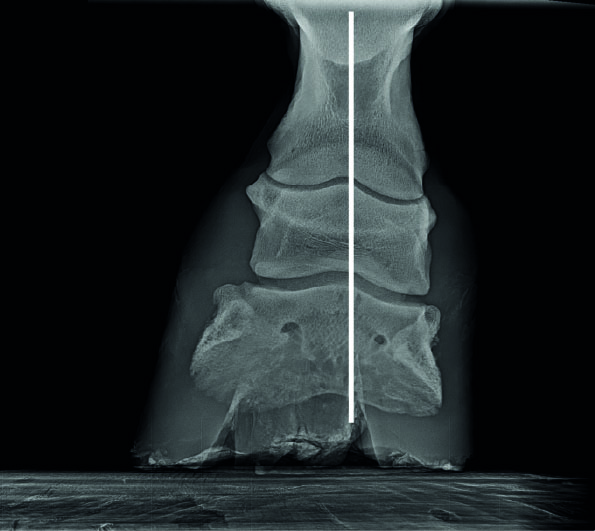

Röntgenbild eines Hufes mit nach hinten gebrochener Huf-Fessel-Achse und einer Überstreckung des Krongelenkes

Röntgenbild eines Hufes mit nach hinten gebrochener Huf-Fessel-Achse und einer Überstreckung des Krongelenkes.

Ergänzend zur Illustration zeigt die folgende Röntgenaufnahme eine Beugung des Hufgelenks, die Ursache der Beugung ist hier allerdings nicht erkennbar. Das intakte Strahlbein spricht allerdings für eine angeborene Beugung.

Röntgenbild eines Hufes mit nach vorne gebrochener Huf-Fessel-Achse und einer Beugung des Hufgelenks

Röntgenbild eines Hufes mit nach vorne gebrochener Huf-Fessel-Achse und einer Beugung des Hufgelenks.